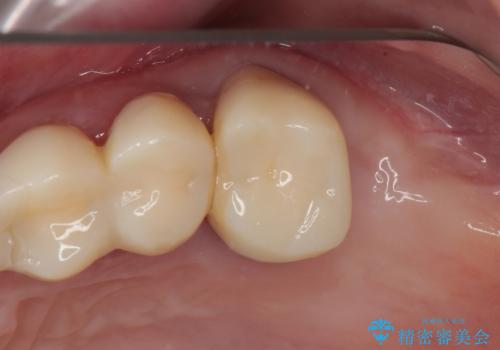

自他共に認める、非常に色白の患者様であったため、黄ばんだ歯の色を白くすることを希望されており、歯周病治療の該当部位に限らず、全顎的にオールセラミッククラウンにて補綴治療を行うこととしました。

多くの外科処置を行ったため、治療期間も長くなり、患者様の負担は非常に大きなものとなりましたが、明るく健康的な口元となり、患者様には大変満足していただけました。